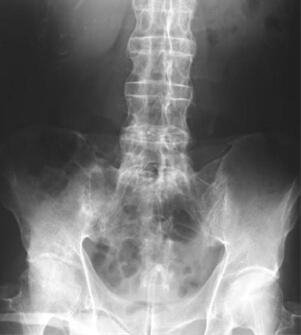

(图:张先生初到院时脊柱变形情况)

所患疾病:强直性脊柱炎

张先生因没日没夜的打游戏,长期保持不正确的坐姿患上强直性脊柱炎,此后肩膀处疼痛难忍,手指僵硬,胯关节处开始疼痛,坐都不能坐了,走路受到限制。长久延误治疗后导致脊柱已有轻微的变形,经药物治疗后病情反复复发,最后在家人的陪伴下来到我院接受治疗。